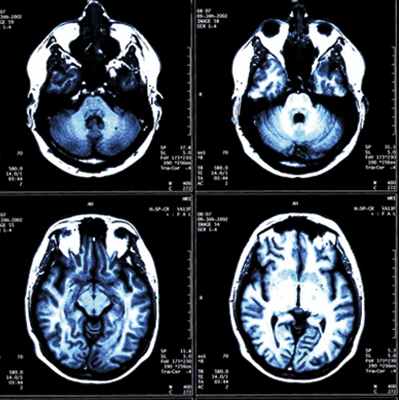

Resonancia Magnética

(RM)